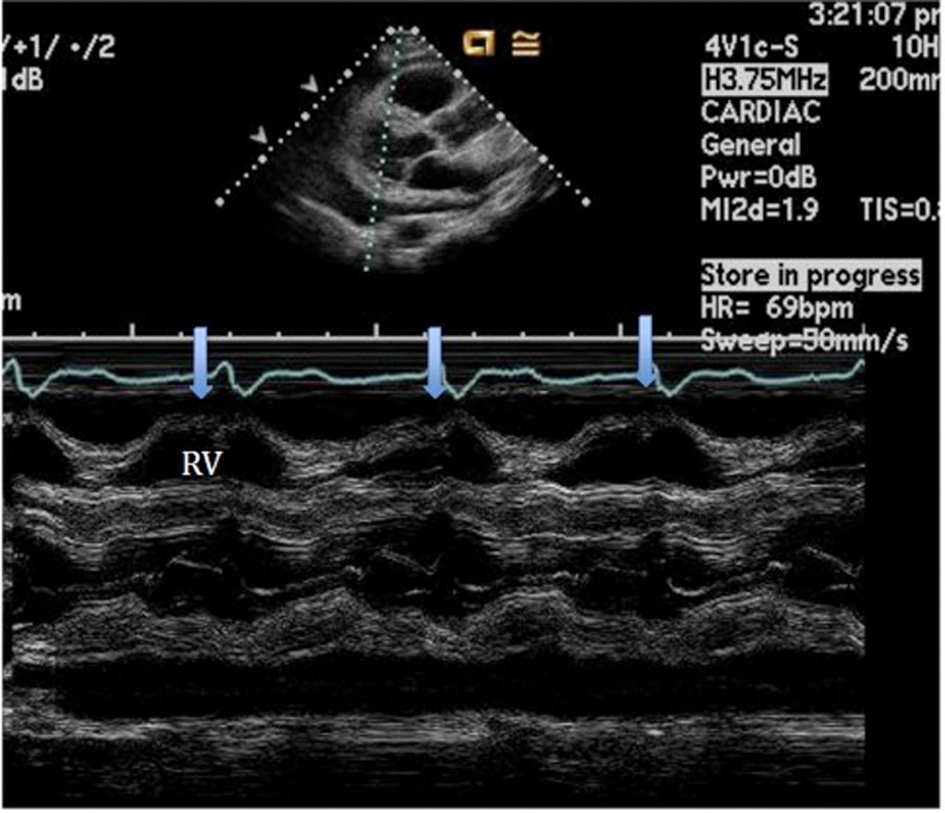

An initial complete blood count showed a mild anemia with hemoglobin of 11.2 g/dl. An anterior-posterior chest x-ray showed bilateral interstitial edema with pleural effusions. A transthoracic echocardiogram was performed and found a large pericardial effusion (Fig. 1) with tamponade physiology (Fig. 2). No intracardiac masses were noted. A right heart catheterization was also performed. The initial right atrial (RA) and intrapericardial pressures were elevated at 38 and 31 mmHg, respectively (Fig. 3). The patient underwent urgent pericardiocentesis after warfarin reversal with vitamin K and fresh frozen plasma. Approximately 1060 ml of blood-tinged fluid were removed. After pericardiocentesis there was no residual pericardial fluid assessed by transthoracic echocardiogram (Fig. 4), despite that the RA pressure remained significantly elevated at 33 mmHg. The RA tracing revealed a prominent Y descent (Fig. 5). Due to the patient’s supratherapeutic INR (international normalized ratio) and transient neurologic deterioration from sedation, simultaneous right and left heart catheterizations were not performed. The hemodynamics were compatible with effusive-constrictive pericarditis. Cytology and flow cytometry in the pericardial fluid revealed the presence of monoclonal kappa B-cells, CD 5 negative, CD 10, CD 19, CD 20, and CD 45 positive. Morphologically, the cells were consistent with large B-cell non-Hodgkin's lymphoma. A bone marrow biopsy ruled out systemic lymphomatous involvement. Positron emission tomography (PET) scan confirmed the diagnosis of primary cardiac lymphoma (PCL) showing thickening of the anterior pericardium with an standardized uptake value (SUV) of 5.0. There was no malignant uptake in any other structure such as lymph nodes, other serosal surfaces, or solid organs.

![]() Click for large image | Figure 2. M-mode of the parasternal long axis view establishing the diagnosis of cardiac tamponade showing the collapse of the RV during diastole. |